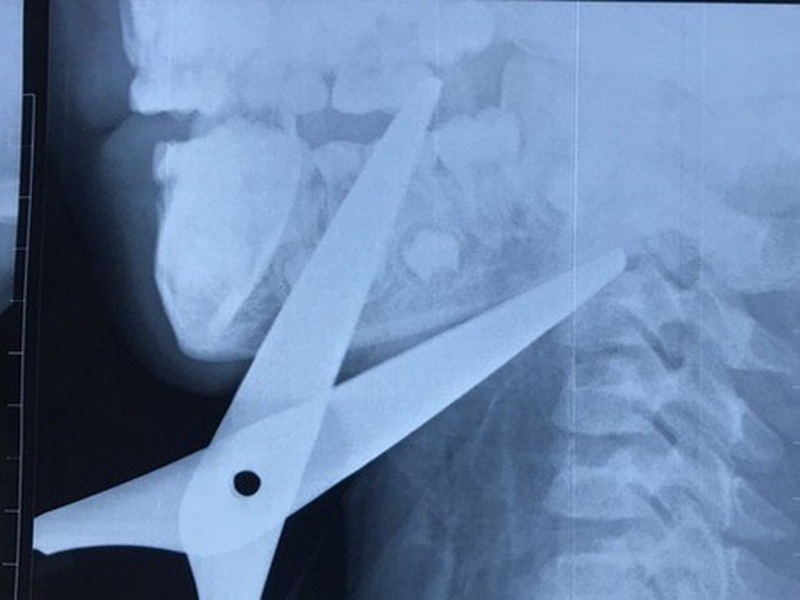

Gia đình cho biết, bé Huy mượn bạn chiếc kéo về làm diều, trong lúc chạy không may vấp ngã đúng chiếc kéo và bị kéo đâm xuyên cổ.

Hình ảnh CT Scanner cho thấy 2 mũi kéo đâm xuyên theo 2 hướng khác nhau vào vùng góc hàm sàn miệng và đi xuyên qua hệ thống mạch máu, thần kinh và dừng lại khi cắm vào thân đốt sống cổ C2. Lưỡi kéo chạy sau nằm sát động mạch cảnh trong bên phải.